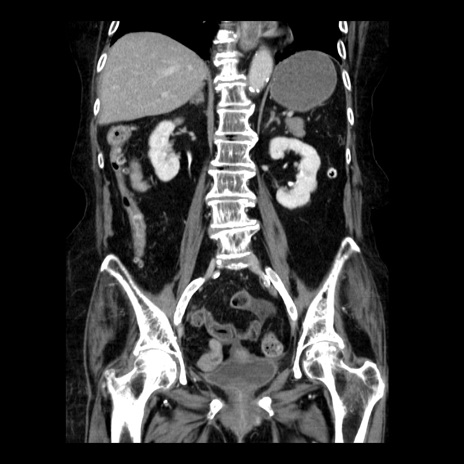

症例14(冠状断像)

【症例】 90歳代女性

【主訴】 腹痛・嘔吐

【現病歴】今朝から左側腹部痛を認めた。 経過観察していたが、嘔吐を認めたため来院。

【既往歴】 子宮癌術後

【身体所見】 意識清明、BP 127/54mmHg、P 98bpm Sp02 95%(RA)、BT 35.8°C、腹部平坦・軟腸ぜん動音聴取良好、右下腹部圧痛(+) 反跳痛なし

【データ】WBC 9800、CRP 0.46